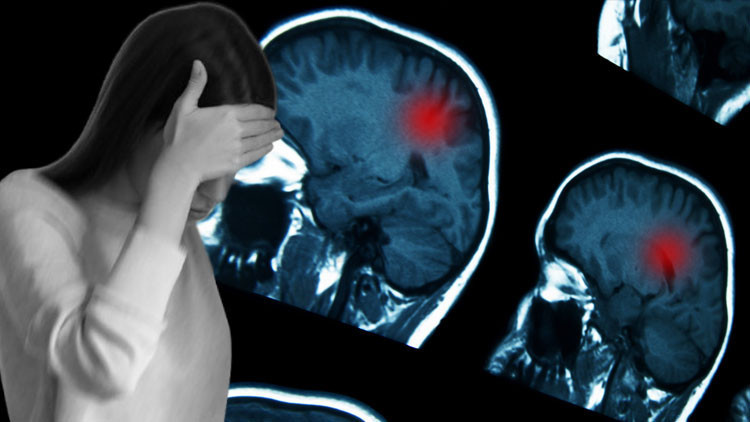

Genç kıza, yalnızca bir ay evvel saldırgan bir beyin tümörü teşhisi konuldu ve acil ameliyat olmazsa yalnızca birkaç haftalık ömrü kaldığı söylendi. Lakin bu teşhise giden yol hiç de kolay olmadı.

Hastanede triyaj odasına alınan ve kusmaya başlayan Moroney için dönüm noktası, annesinin tarama yapılması konusundaki sert ısrarı oldu. Yapılan BT taraması sonucunda beyninde bir tümör olduğu tespit edildi.

Daha sonra Cambridge’deki Addenbrooke’s Hastanesi’ne sevk edilen genç kıza burada acı haber verildi: Şayet tümör çabucak alınmazsa bir ay içinde hayatını kaybedecekti. 17 Şubat’ta gerçekleşen başarılı bir operasyonla tümörün büyük bir kısmı temizlendi.

Ameliyat sonrası yapılan biyopsi, durumun varsayım edilenden daha karmaşık olduğunu ortaya koydu. Moroney’ye, ekseriyetle 5 yaş altı çocuklarda görülen ve yetişkinlerde rastlanması son derece az olan 4. Evre Atipik Teratoid/Rhabdoid Tümör (AT/RT) teşhisi konuldu.